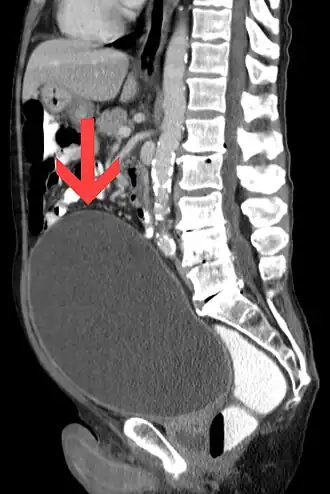

La retención urinaria es la incapacidad de un individuo de orinar pese a tener la vejiga llena, con su consecuente aumento de volumen, lo que se conoce como globo vesical. Antiguamente se denominaba iscuria.[1]

El examen físico muestra una masa en el bajo vientre, por encima del pubis, redondeada, extendida y con un sonido mate a la percusión.

La más frecuente de las complicaciones es la infección urinaria: cistitis primeramente y posteriormente pielonefritis. Cuando es crónica, la retención provoca una distensión de la vejiga con atonía del detrusor, hipertrofia del detrusor o formación divertículos vesicales. La retención urinaria podría provocar un reflujo de la orina hacia los riñones, que causaría una hidronefrosis.